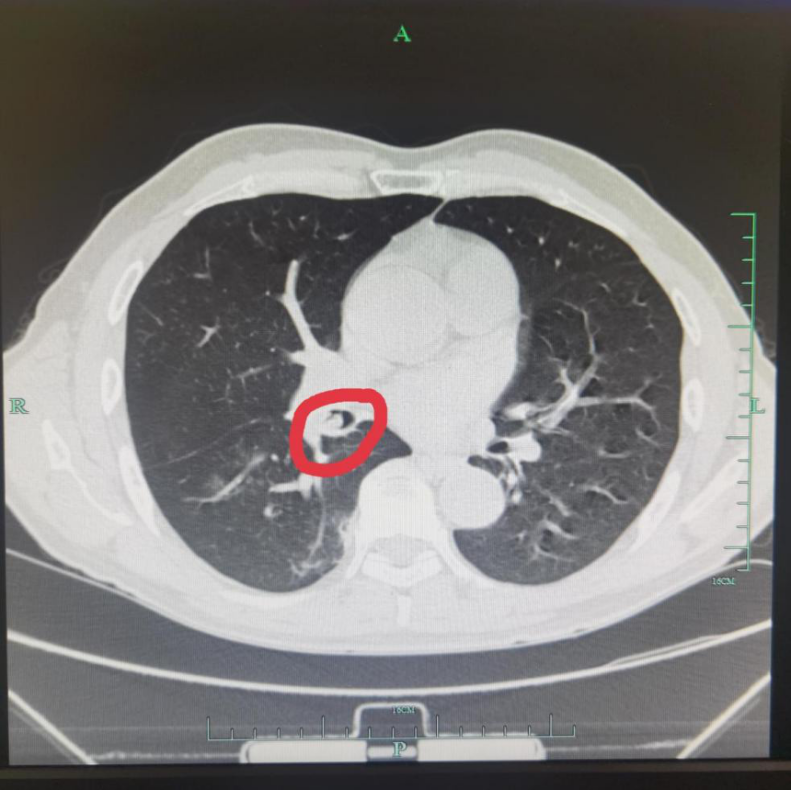

右边胸口还是感觉闷闷的,憋得慌。于是在家人陪同下,来到了医院就诊。接诊医师仔细询问病情后,立即给吴先生安排了胸部CT检查,结果提示:右下支气管内可及高密度影,异物考虑。

胸部CT:右下支气管开口处可及高密度影 住院后立即给吴先生预约了气管镜检查,没多久,便顺利完成了全麻支气管镜检查。

检查过程中,在镜下右下支气管开口清晰地见到了异物,医生用活检钳及圈套器顺利将其取出。